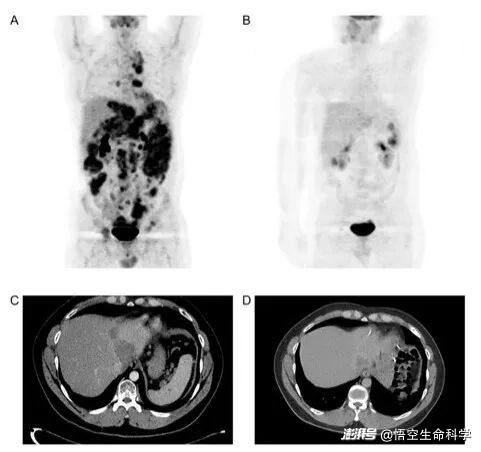

▲在接受免疫细胞联合治疗后,一名患有促纤维增生性小圆细胞肿瘤的患者,通过 PET 扫描发现 FDG 亲和力显著降低,并且通过 CT 扫描使用 RECIST v1.1 发现肿瘤大小显著缩小。